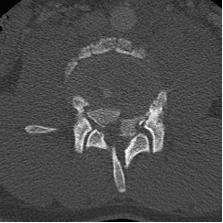

Un chico de 18 años se cayó desde tres pisos. Pérdida casi total de todas las funciones neurológicas por debajo del nivel de lesión con afectación casi total del intestino y la vejiga

Cirugía

El paciente fue operado y el conducto espinal limpiado de todos los fragmentos óseos. La columna vertebral se fijó de lado y la parte trasera para eliminar la inestabilidad.